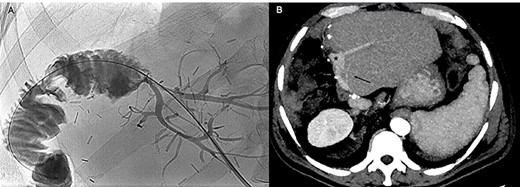

Contrast-enhanced computed tomography (CECT) and magnetic resonance cholangiography revealed a type IIIa Klatskin tumor, closely adherent to portal vein bifurcation and infiltrating the proximal left portal vein. The stenosis was hemodynamically significant at US-Doppler examination (Fig. 1A and B).

Since significant left portal vein narrowing at its origin due to tumor infiltration (A, B) contraindicated upfront right portal vein embolization, which was deemed potentially ineffective and at risk of favoring portal trunk thrombosis, porto-portal shunt by the mean of an autologous internal jugular vein graft interposition, followed by right and middle hepatic veins embolization, was performed (C, D).

Given the important narrowing of the proximal left portal vein, which would have jeopardized any attempt at inducing FLR hypertrophy, the patient first underwent surgical left portal vein recanalization. This was achieved by interrupting main and left portal vein outside the infiltrated area (which was deliberately not touched) and interposing an autologous internal jugular vein graft; portal bifurcation was by-passed, and portal flow was completely diverted to the left hemi-liver (Fig. 1C).

Unfortunately, CECT performed 3 weeks after the operation showed no increase in FLR volume, with partial reperfusion of multiple small intrahepatic right portal branches, characterized by reversed flow. Considering the technical difficulty of portal vein embolization (PVE) in this setting, percutaneous embolization of the right and middle hepatic veins (HVE) was considered as a salvage strategy (Fig. 1D).